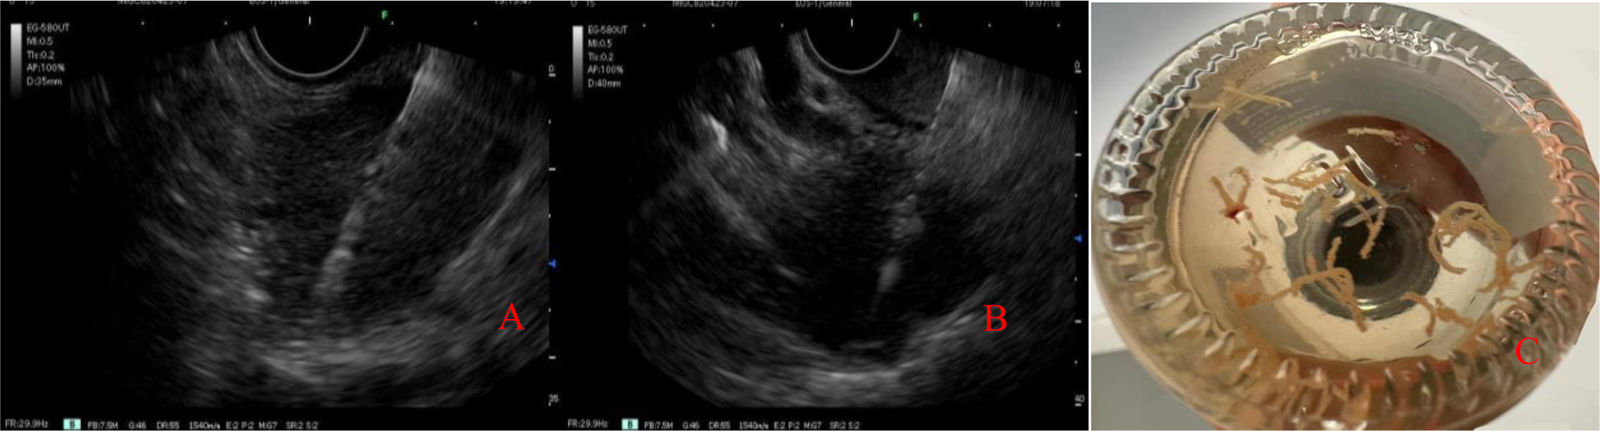

The USE was carried out under general anesthesia, with a linear echoendoscope, enabling detailed evaluation of the pancreatic parenchyma (diffuse enlargement), main pancreatic duct, and contiguous organs (Fig. 1). Using a 22 G Franseen fine-needle biopsy needle, samples were obtained from the head of the pancreas, via the transduodenal approach, and the body of the pancreas, via the transgastric approach, preventing vascular damage through the Doppler technique (Fig. 2). One needle pass was carried out in each region, using the fanning technique, with the slow removal of the stylet to maximize the sample yield (Fig. 2). No intraoperative or postoperative complications were registered.

The histopathologic analysis of the samples revealed lymphoplasmacytic infiltration positive for IgG4, consistent with AIP, emphasizing the usefulness of the minimally invasive approach through USE for diagnostic accuracy, as well as for guiding adequate treatment. Treatment was started with prednisone (1 mg/kg/day) for four weeks, with reduced disease progression for the following month. The patient progressed favorably, with no new episodes of pancreatitis during a 15-month follow-up.